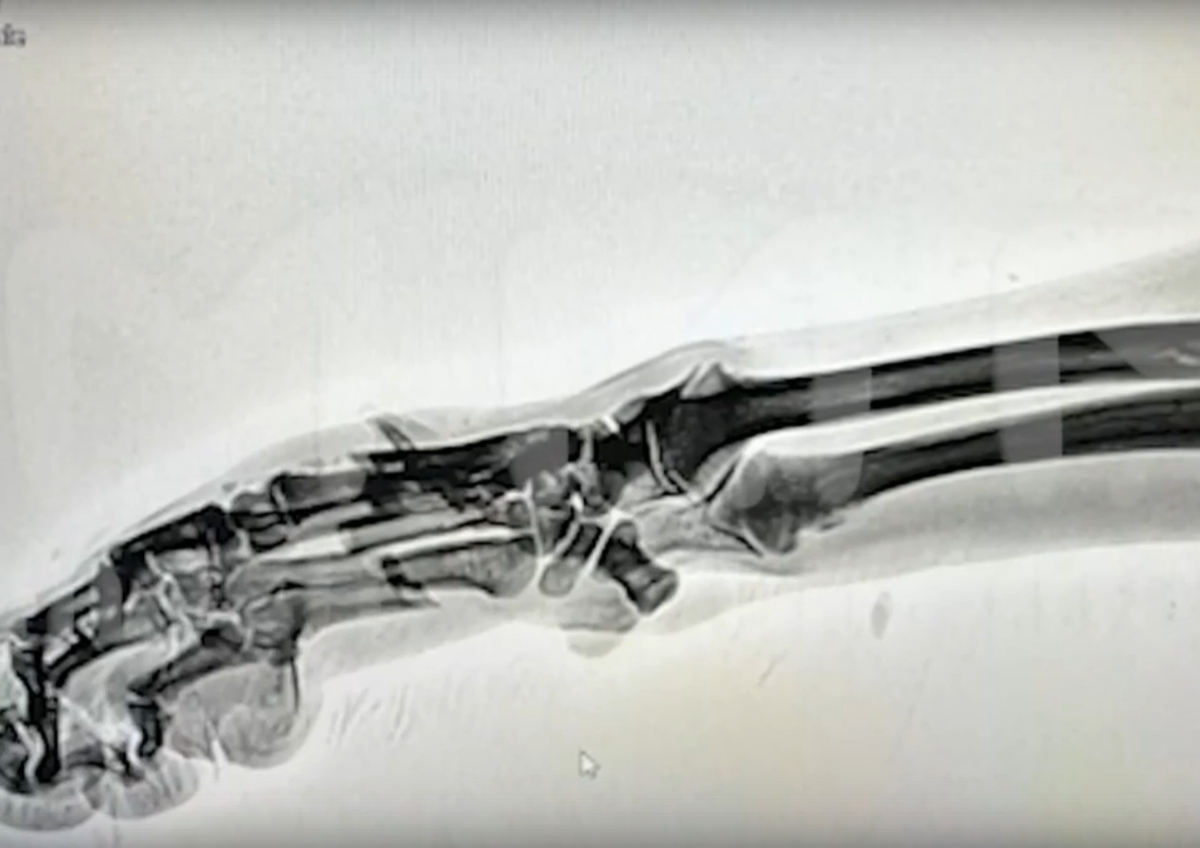

Интернет послужил им заменой медицинского справочника. Ориентируясь по обучающим видео, наши ребята сделали рентген и поставили диагноз: переломы со смещением.

Рентген  показал характер травмы

А затем - наложили гипс. На видео, выложенным в интернете, видно, что они даже используют металлическое ребро жёсткости, которое закладывают по фиксирующую повязку.